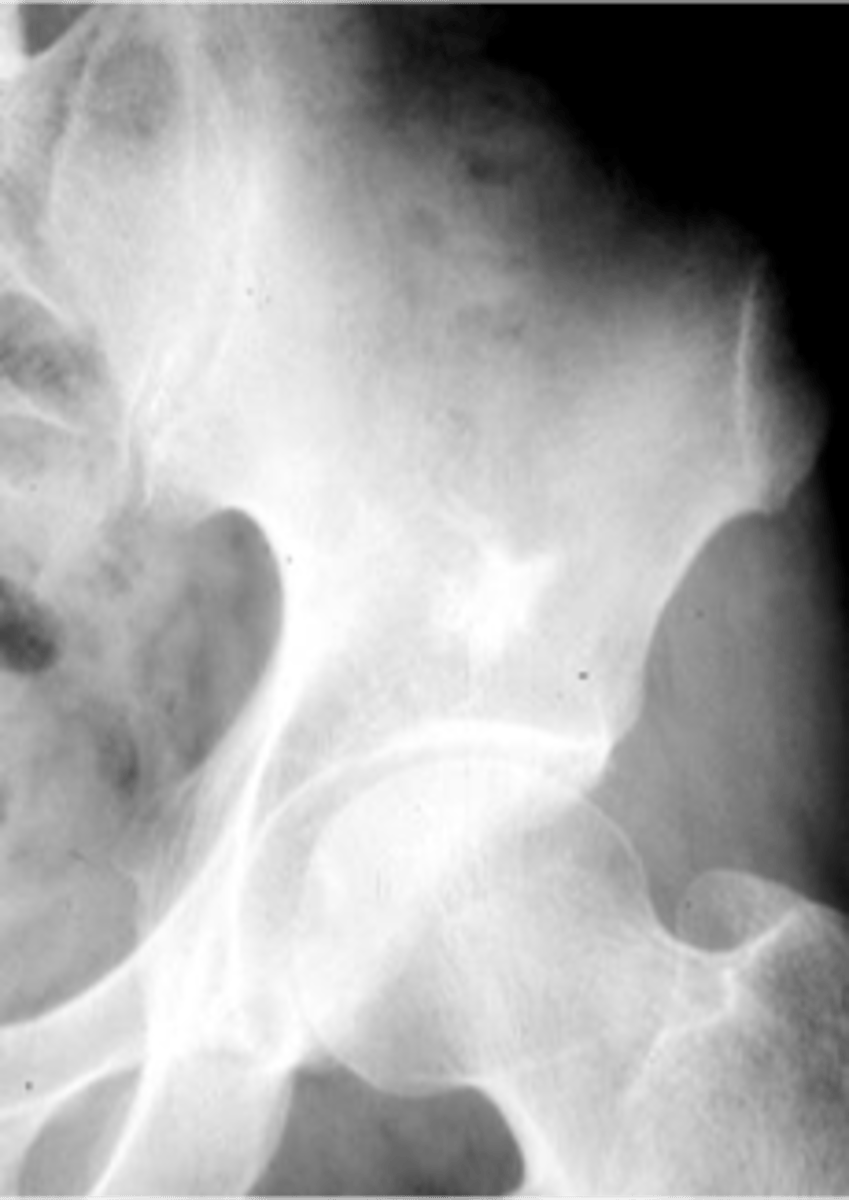

Bone island

- Any age

- Adults > children

- Asymptomatic

- Usually solitary

- Any bone (except skull)

Enostoma/enostosis

Normal tissue in an abnormal area

- Epiphyseal, metaphyseal

- Medullary

- Round/oval

- Radiating border ("brush border")

- Radiodense

- May change size

- May be warm on bone scan

State the radiologic features of a bone island (enostoma/enostosis)

- Ischium

- Ilium

- Sacrum

- Proximal femur

- Humerus

- Vertebra

- Talus

- Scaphoid

State the locations for a bone island

Giant bone islands

ID

- Bone island

- Kidney stone*

22 y.o. male with L/S pain, post motor vehicle accident

- Differential diagnosis?

Osteopoikilosis

Diagnosis?